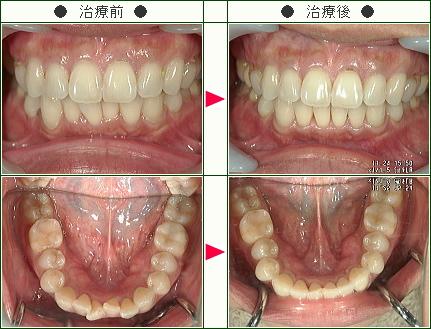

☆デコボコ症例(高橋様 48歳 男性)

▼患者様の感想

治療期間、特にブラケットを設置している期間が短かったので大変満足しています。

想像以上に治療を要する虫歯があり、今回その治療もすべて行うことが出来たので良かったです。